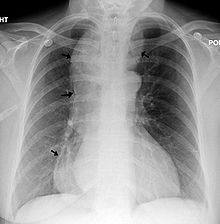

من الأعراض الأخرى الأقل شيوعا قلس الطعام غير المهضوم ونقص الوزن وحرقة الفؤاد والألم الصدري. قد يؤدي قلس المواد الطعامية إلى السبيل التنفسي أثناء الاستلقاء ليلا إلى حدوث الاختناق أو ذات الرئة الشفطية (ذات الرئة بالارتشاف). غالبا ما يكون نقص الوزن خفيفا ما بين 5 إلى 10 كغ. يمكن أن يكون سبب حس حرقة الفؤاد لدى بعض المرضى هو وجود داء الجزر المعدي المريئي مستبطنا لديهم، وقد يكون بسبب التخريش المباشر للمواد الطعامية ومستقلباتها المحصورة في المريء. قد يكون الألم الصدري هو العرض الذي يراجع به بعض المرضى بشكل مشابه للألم القلبي. يذكر أيضا أن بعض المرضى الذين يراجعون الطبيب بما يعرف باللقمة الهستيرية يعانون من من تعذر الارتخاء المريئي.[2][4][5]

التشخيص

ابتلاع الباريوم